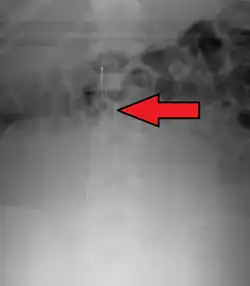

IVC filters are placed endovascularly, meaning that they are inserted via the blood vessels. Historically, IVC filters were placed surgically, but with modern filters that can be compressed into much thinner catheters, access to the venous system can be obtained via the femoral vein (the large vein in the groin), the internal jugular vein (the large vein in the neck) or the arm veins with one design. Choice of route depends mainly on the number and location of any blood clot within the venous system. To place the filter, a catheter is guided into the IVC using fluoroscopic guidance, then the filter is pushed through the catheter and deployed into the desired location, usually just below the junction of the IVC and the lowest renal vein.[44]

Review of prior cross-sectional imaging or a venogram of the IVC is performed before deploying the filter to assess for potential anatomic variations, thrombi within the IVC, or areas of stenoses, as well as to estimate the diameter of the IVC. Rarely, ultrasound-guided placement is preferred in the setting of contrast allergy, chronic kidney disease, and when patient immobility is desired. The size of the IVC may affect which filter is deployed, as some (such as the Birds Nest) are approved to accommodate larger cavae. There are situations where the filter is placed above the renal veins (e.g. pregnant patients or women of childbearing age, renal or gonadal vein thromboses, etc.). Also, if there is duplication of the IVC, the filter is placed above the confluence of the two IVCs [45] or a filter can be placed within each IVC.[46]